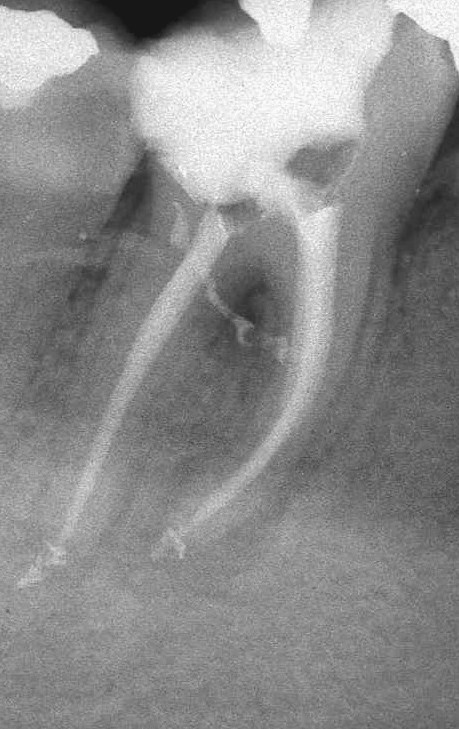

Apertura della corona fino ad arrivare alla camera pulpare (tale trattamento viene eseguito tramite anestesia locale). Si rimuove la polpa e si cercano i canali radicolari del dente, una volta trovati si estirpano i nervi. Si allargano e si puliscono i canali del dente, (tramite strumenti al Nichel titanio o strumenti manuali) prendendo anticipatamente le misure dei canali (per non uscire oltre apice). Si disinfettano i canali e si eseguono vari lavaggi tra un passaggio e un altro per elimininare il fango dentinale. Il medico a questo punto verifica la possibilità di chiudere definivamente i canali o lasciare il dente in prova, inserirendo nei canali un disinfettante e eseguendo una chiusura provvisoria. Al momento di chiudere il dente definivamente, questo viene preparato rieseguendo le misure dei canali da chiudere ed usando per la stessa lunghezza del canale, un cono di guttaperga del diametro necessario. Si scalda il cono in guttaperga e si inserisce nel canale. Durante il trattamento endodondico vengono effettuati una serie di esami radiografici per verificare i risultati, le lunghezze, la forma dei canali.

L'esame radiografico, fondamentale per porre diagnosi in odontoiatria, in endodonzia è irrinunciabile perché è l'unico strumento che ci permette di "vedere" all'interno della radice del dente, è quindi molto importante la possibilità di effettuare lastre con apparecchiature digitali che emettono un quarto della dose di raggi emessa da un radiografico tradizionale e che permettono di conservare la radiografia endorale in una cartella informatica del paziente senza possibili alterazioni nel tempo.